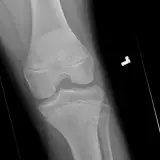

MSK Radiographs

Review cases with classic "textbook" pathology. Once you've mastered the basics, move on to practice cases with more challenging or subtle findings.

Oftentimes the key to nailing a difficult radiology case is having seen a similar case before. Practice with over 1,500 carefully selected cases covering a comprehensive list of diagnoses.

Master classic and atypical appearances of pathologies more efficiently than haphazardly reviewing cases at work. Cases include sample reports, focused discussions, annotated images, and reputable references.